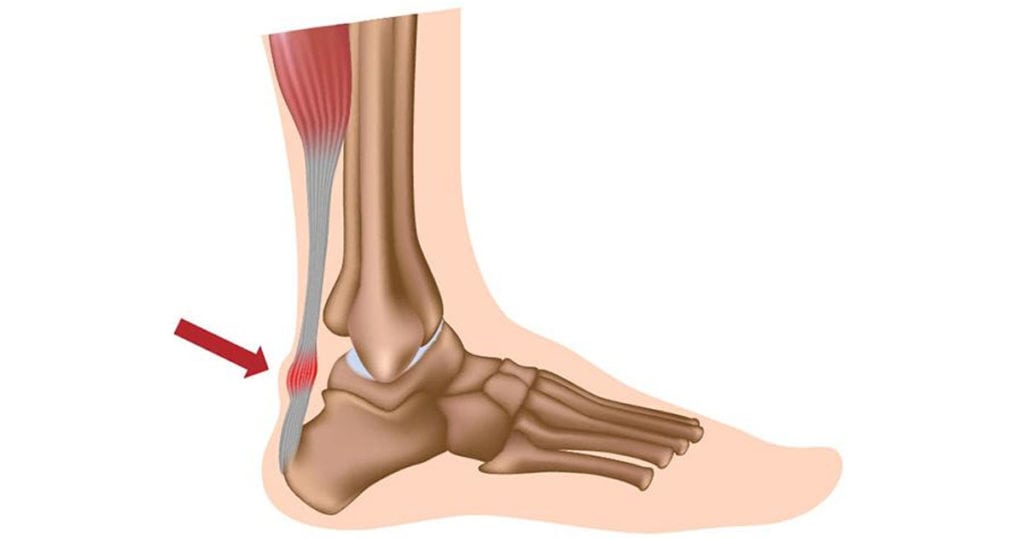

Ахиллово сухожилие — связующее звено между пяточной костью и мышцами икры. За счет этого мощного соединительнотканного тяжа обеспечивается подвижность голеностопа. Он помогает суставу выдерживать интенсивные статические и динамические нагрузки. Но при превышении предела прочности целостность волокон нарушается, а ахиллово сухожилие утрачивает способность стабилизировать стопу. Ведущий симптом растяжения — острая, пронизывающая боль, а затем на травмированном участке формируется отек и обширная гематома.

Ахиллово сухожилие является самым крупным в опорно-двигательной системе человека, а формируют его камбаловидная и икроножная мышцы. Основная функция тяжа — подъем пятки во время движения. Он также участвует в опускании передней части стопы. Если бы этого тяжа не было, то человек не смог бы:

Главная причина разрыва этого прочного тяжа — резкое сокращение икроножной и камбаловидной мышц. Такая ситуация возникает во время прыжка или бега при старте, при падении из-за сильного сгибания стопы с тыльной стороны. Волокна разрываются в результате прямой травмы, например, удара ногой или тяжелым предметом.